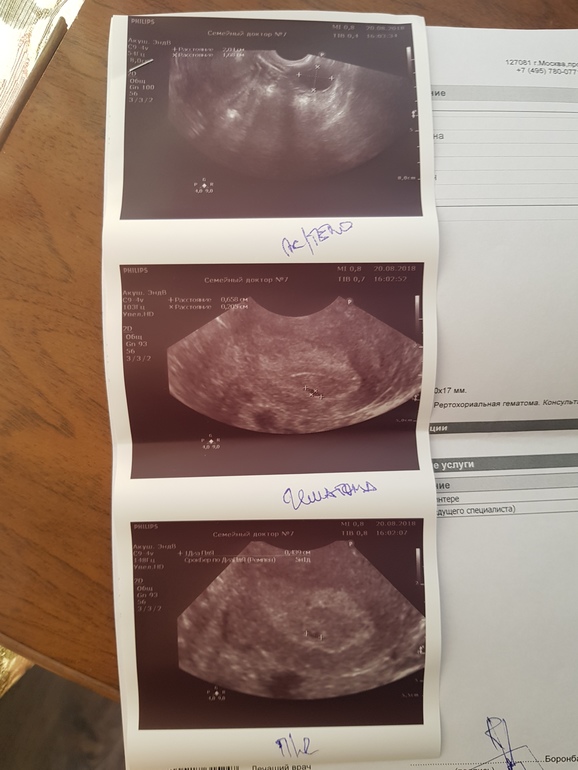

После узи решила зайти ко врачу. И вот что мне она сказала, что гематома-это страшно и это угроза, выписала утрожестан, магний Б6, папаверин и фольку. Так же назначилп узи на 30.08 и сдать кучу анализов. Дико теперь блюсь, все принимаю, что назначили, но тесты ярчали очень хорошо. С 14 лет проблемы с циклом, вот и переживаю, надеюсь утрик поможет. Даже не знаю как дотерпеть до 30😭😭😭

P.S. фото узи в 5н.и 1д

У меня 10,7 х 7 мм, рекомендовано в стационар. Читаю, все дома с гематомой. Узи 31. Даже не знаю как поступить